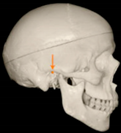

Three points determined the Acta plane: O, F right (FR), and F left (FL) (Table 2). Point O is the midpoint between the most craniodorsal point of the dorsum Sella and the most posterior dorsal point of the Basion in the midsagittal plane (Figure 1). Both points F are a result of the intersection between two lines: the line that connects the most inferior points of the lower orbital margins, right and left, and a line perpendicular to this line that runs through the most external points of the orbital margins, right and left (Figure 2). The new transverse reference plane, the Acta plane (Figure 2), is created by connecting the O-point (Figure 1) with FR and FL (Figure 2).

Figure 1.

Point O (green dot) is the midpoint between the dorsum Sella (Se) (red dot) and the Basion point (Ba) (yellow dot).